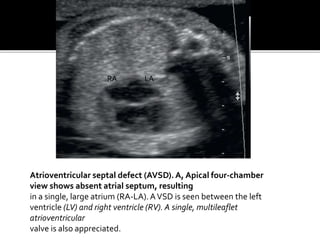

Atrioventricular septal defect (AVSD).A, Apical four-chamber

view shows absent atrial septum, resulting

in a single, large atrium (RA-LA).AVSD is seen between the left

ventricle (LV) and right ventricle (RV). A single, multileaflet

atrioventricular

valve is also appreciated.

Atrioventricular septal defect(AVSD).A, Apical four-chamber view shows absent atrial septum, resulting in a single, large atrium (RA-LA).AVSD is seen between the left ventricle (LV) and right ventricle (RV). A single, multileaflet atrioventricular valve is also appreciated. RA LA